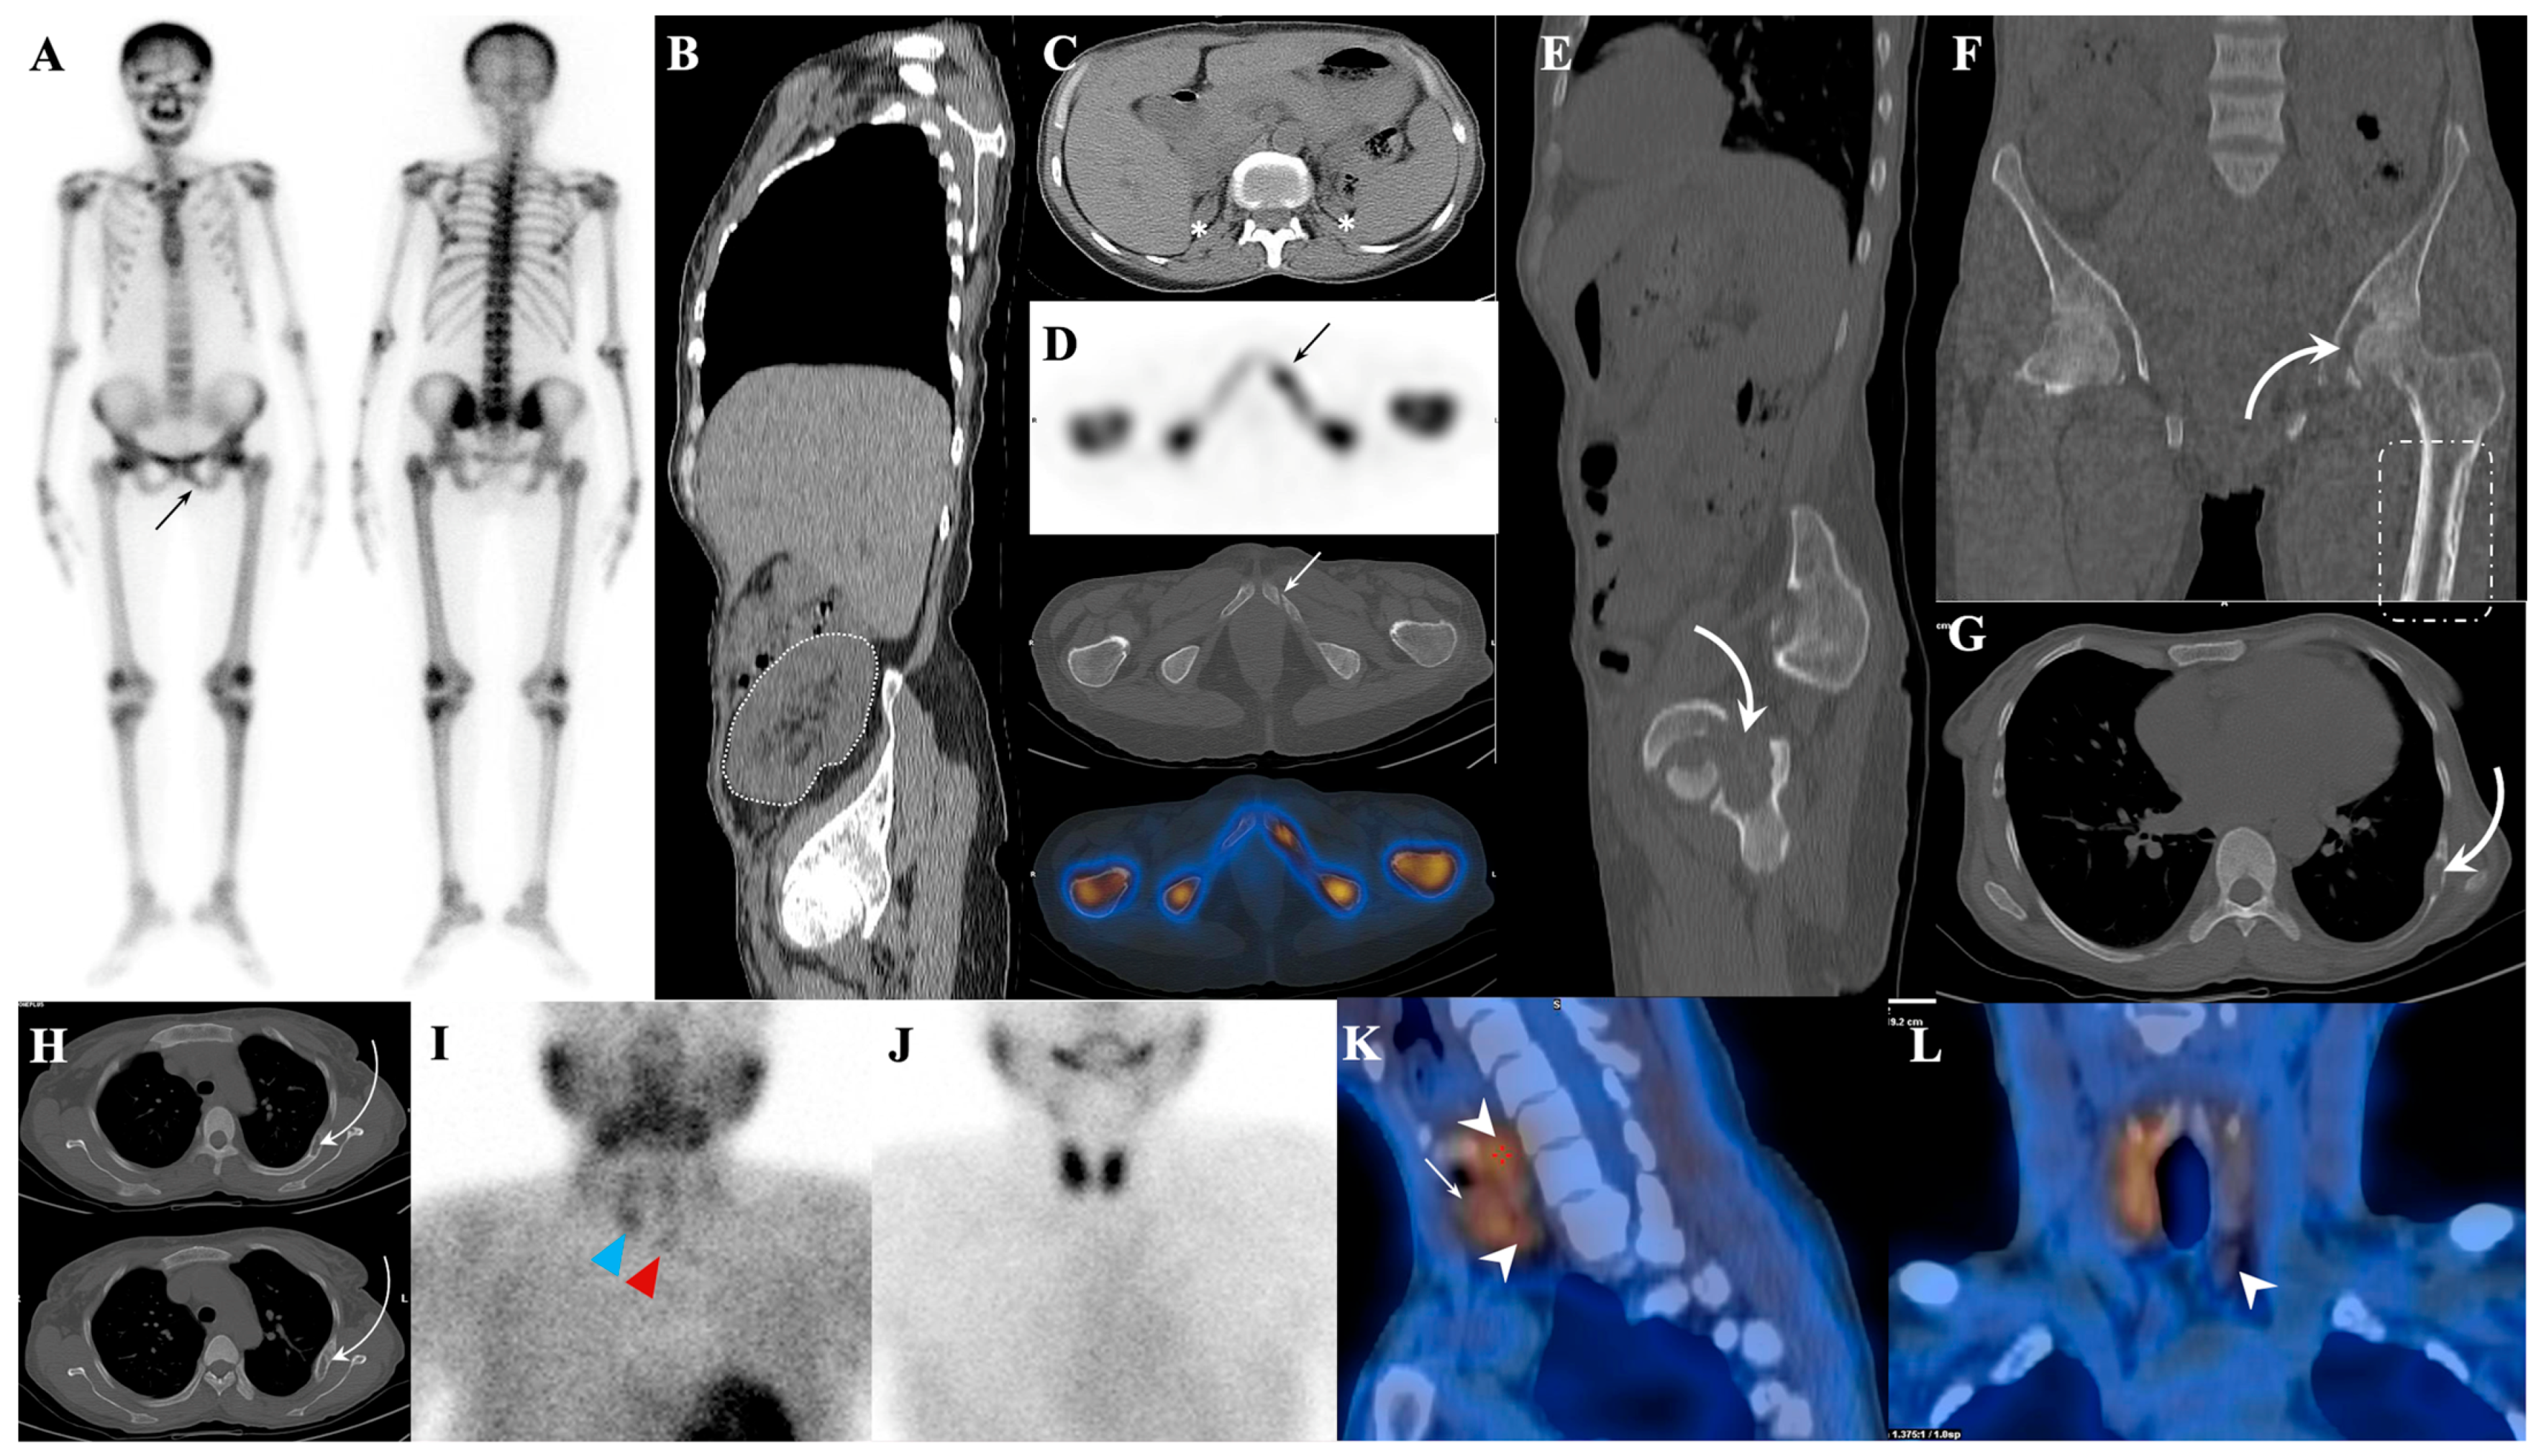

7.1.1. Superscan Pattern in Patients with Prostate Cancer

7.1.2. Dynamic Changes in Prostate Cancer Patients with Superscan

7.2. Metabolic Superscan

7.3. Distinguishing Metabolic Superscan from Metastatic Superscan